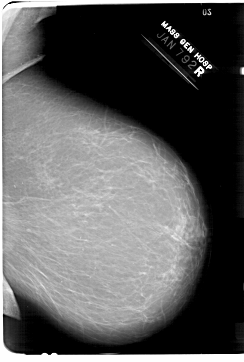

A_1380_1.RIGHT_MLO

RIGHT_MLO LINES 6871 PIXELS_PER_LINE 4636 BITS_PER_PIXEL 12 RESOLUTION 43.5 NON_OVERLAY